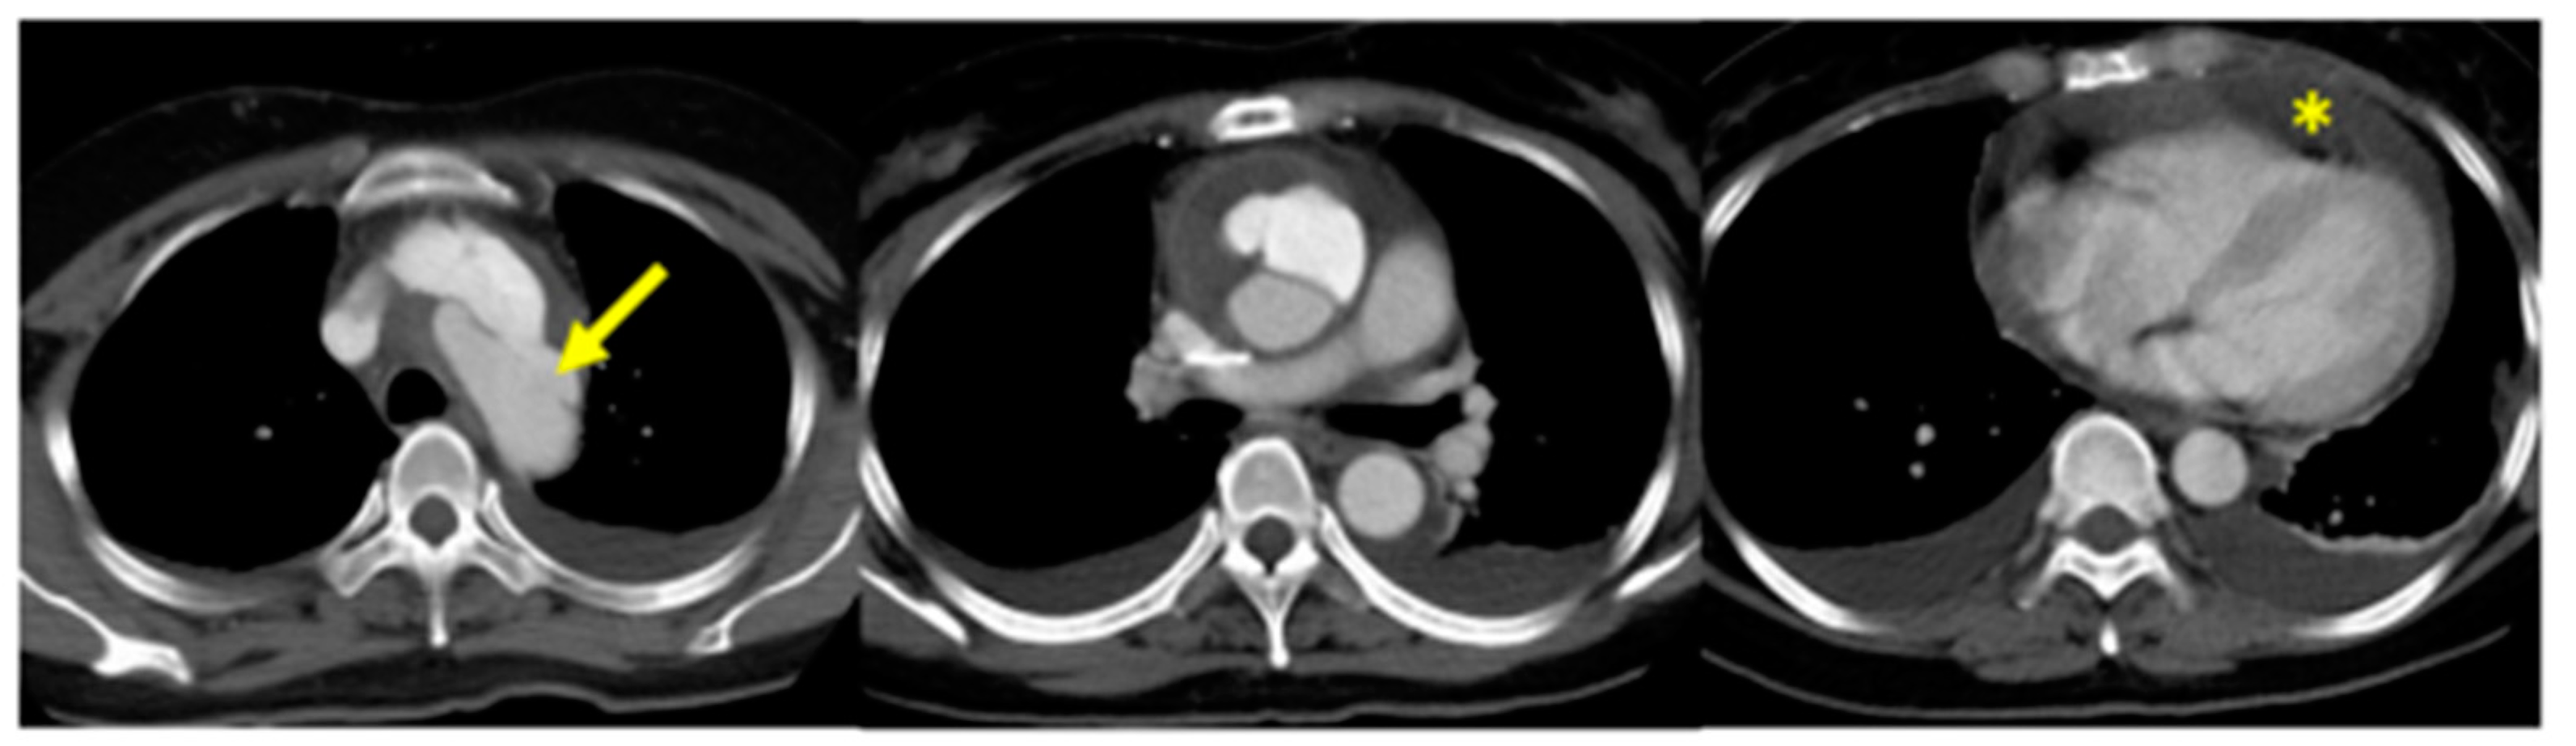

In the event that there is aortic involvement (aneurysms or dissections), this is associated with a high mortality rate determined by the extreme tissue fragility and by the high rate of complications (bleeding, sternal wound dehiscence) in the immediate perioperative time (Figure 10) [45,46].

Figure 10.

Stanford type A dissection in patient with vEDS. Arrow: intimal tear in the aortic arch; asterisk: pericardial effusion. Adapted with permission from [46].